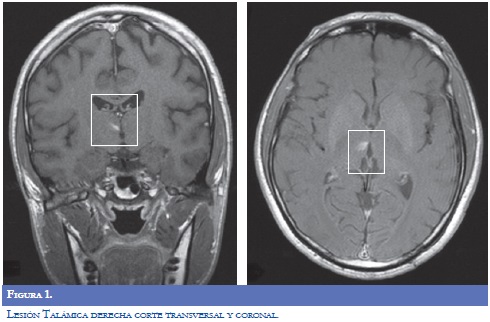

Paraclínicos de ingreso: glucometría 272 mg/ dl, Hb Glicosilada 15,8%. La RM del encéfalo (9/09/2009): evidenció lesión que restringía la difusión, visible en FLAIR y T2, infarto subagudo en región superior y anterior derecha del bulbo raquídeo. Imagen hiperintensa en T1, que no realzaba, en el tálamo derecho. Angioresonancia: fenestración de la arteria vertebral derecha distal, hallazgo incidental Neuroradiología reportó que la lesión hiperintensa talámica derecha pudiera obedecer a alteración metabólica por hiperglicemia, pero fue asumido por neurología clínica como infarto lacunar (Figuras 1-2).

Se inició terapia física basada en estiramientos pasivos sostenidos, movilizaciones pasivas por medio de patrones unilaterales, posicionamiento, fortalecimiento muscular, entrenamiento de agarre fino y grueso y entrenamiento del patrón de marcha sin caminador, equilibrio y propiocepción. Mejoró a paresia braquial izquierda 3/5 y 4/5 crural ipsilateral, hipotónico, con Babinski izquierdo. Parestesias de hemicuerpo izquierdo. Logró marcha parética, muy limitada. Valoración de egreso (18/09/2009): lesión talámica derecha que sugiere infarto lacunar con transformación hemorrágica. Se descartó cardioembolismo, estenosis intracraneana o extracraneana, trombofilia o autoinmunidad. Por ser diabético mal controlado, se atribuyó la causa del ACV a microangiopatía.

Los diagnósticos de egreso (18/09/2009) fueron: ACV bulbar superior y anterior derecho en paciente joven; infarto lacunar talámico derecho con transformación hemorrágica; Diabetes insulino requiriente descompensada.

La causa atribuida al cuadro neurológico que presentó el paciente correspondió a infartos lacunares secundarios a microangiopatia diabética en el talámo y la pirámide bulbar derechos. El infarto de la pirámide bulbar derecha explica una lesión parcial de la vía córtico espinal previa a la decusación. De esta forma dicho déficit explica la hemiplejia izquierda inicial. La ubicación de esta lesión no explica la sintomatología sensitiva. La lesión talámica derecha, en la zona medial, explica la sintomatología sensitiva. La arteria cerebral posterior, mediante su rama geniculotalámica, perfunde el territorio talámico posterolateral. La arteria comunicante posterior, a través de la rama tuberotalámica, riega el territorio talámico anterolateral. La arteria carótida interna, por su rama coroidea anterior, se distribuye en el territorio talámico lateral (13).